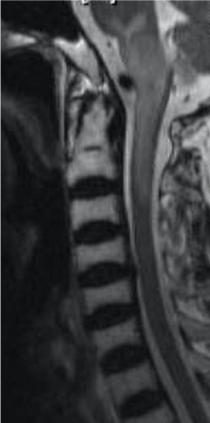

MRI is the best imaging modality for diagnosis of cord infarct. On T1-weighted images (Figure 4b), the cord is slightly expanded and demonstrates low signal intensity due to the presence of oedema. In some patients T1 hyperintense foci may be seen within the infarcted cord due to hemorrhagic conversion. These will show blooming on gradient recalled echo imaging. On T2-weighted images (Figure 4a), high signal is seen within the cord, which may involve the central gray matter or the entire cross-sectional area of the cord [2] . On diffusionweighted imaging, the infarcted cord would show high signal with corresponding low signal on ADC map [2].

Figure 4. (a)Sagittal T2-weighted MRI shows hyperintense signal within the cervical cord. (b)Corresponding low signal within the cervical cord on T1-weighted MRI is consistent with cord infarct